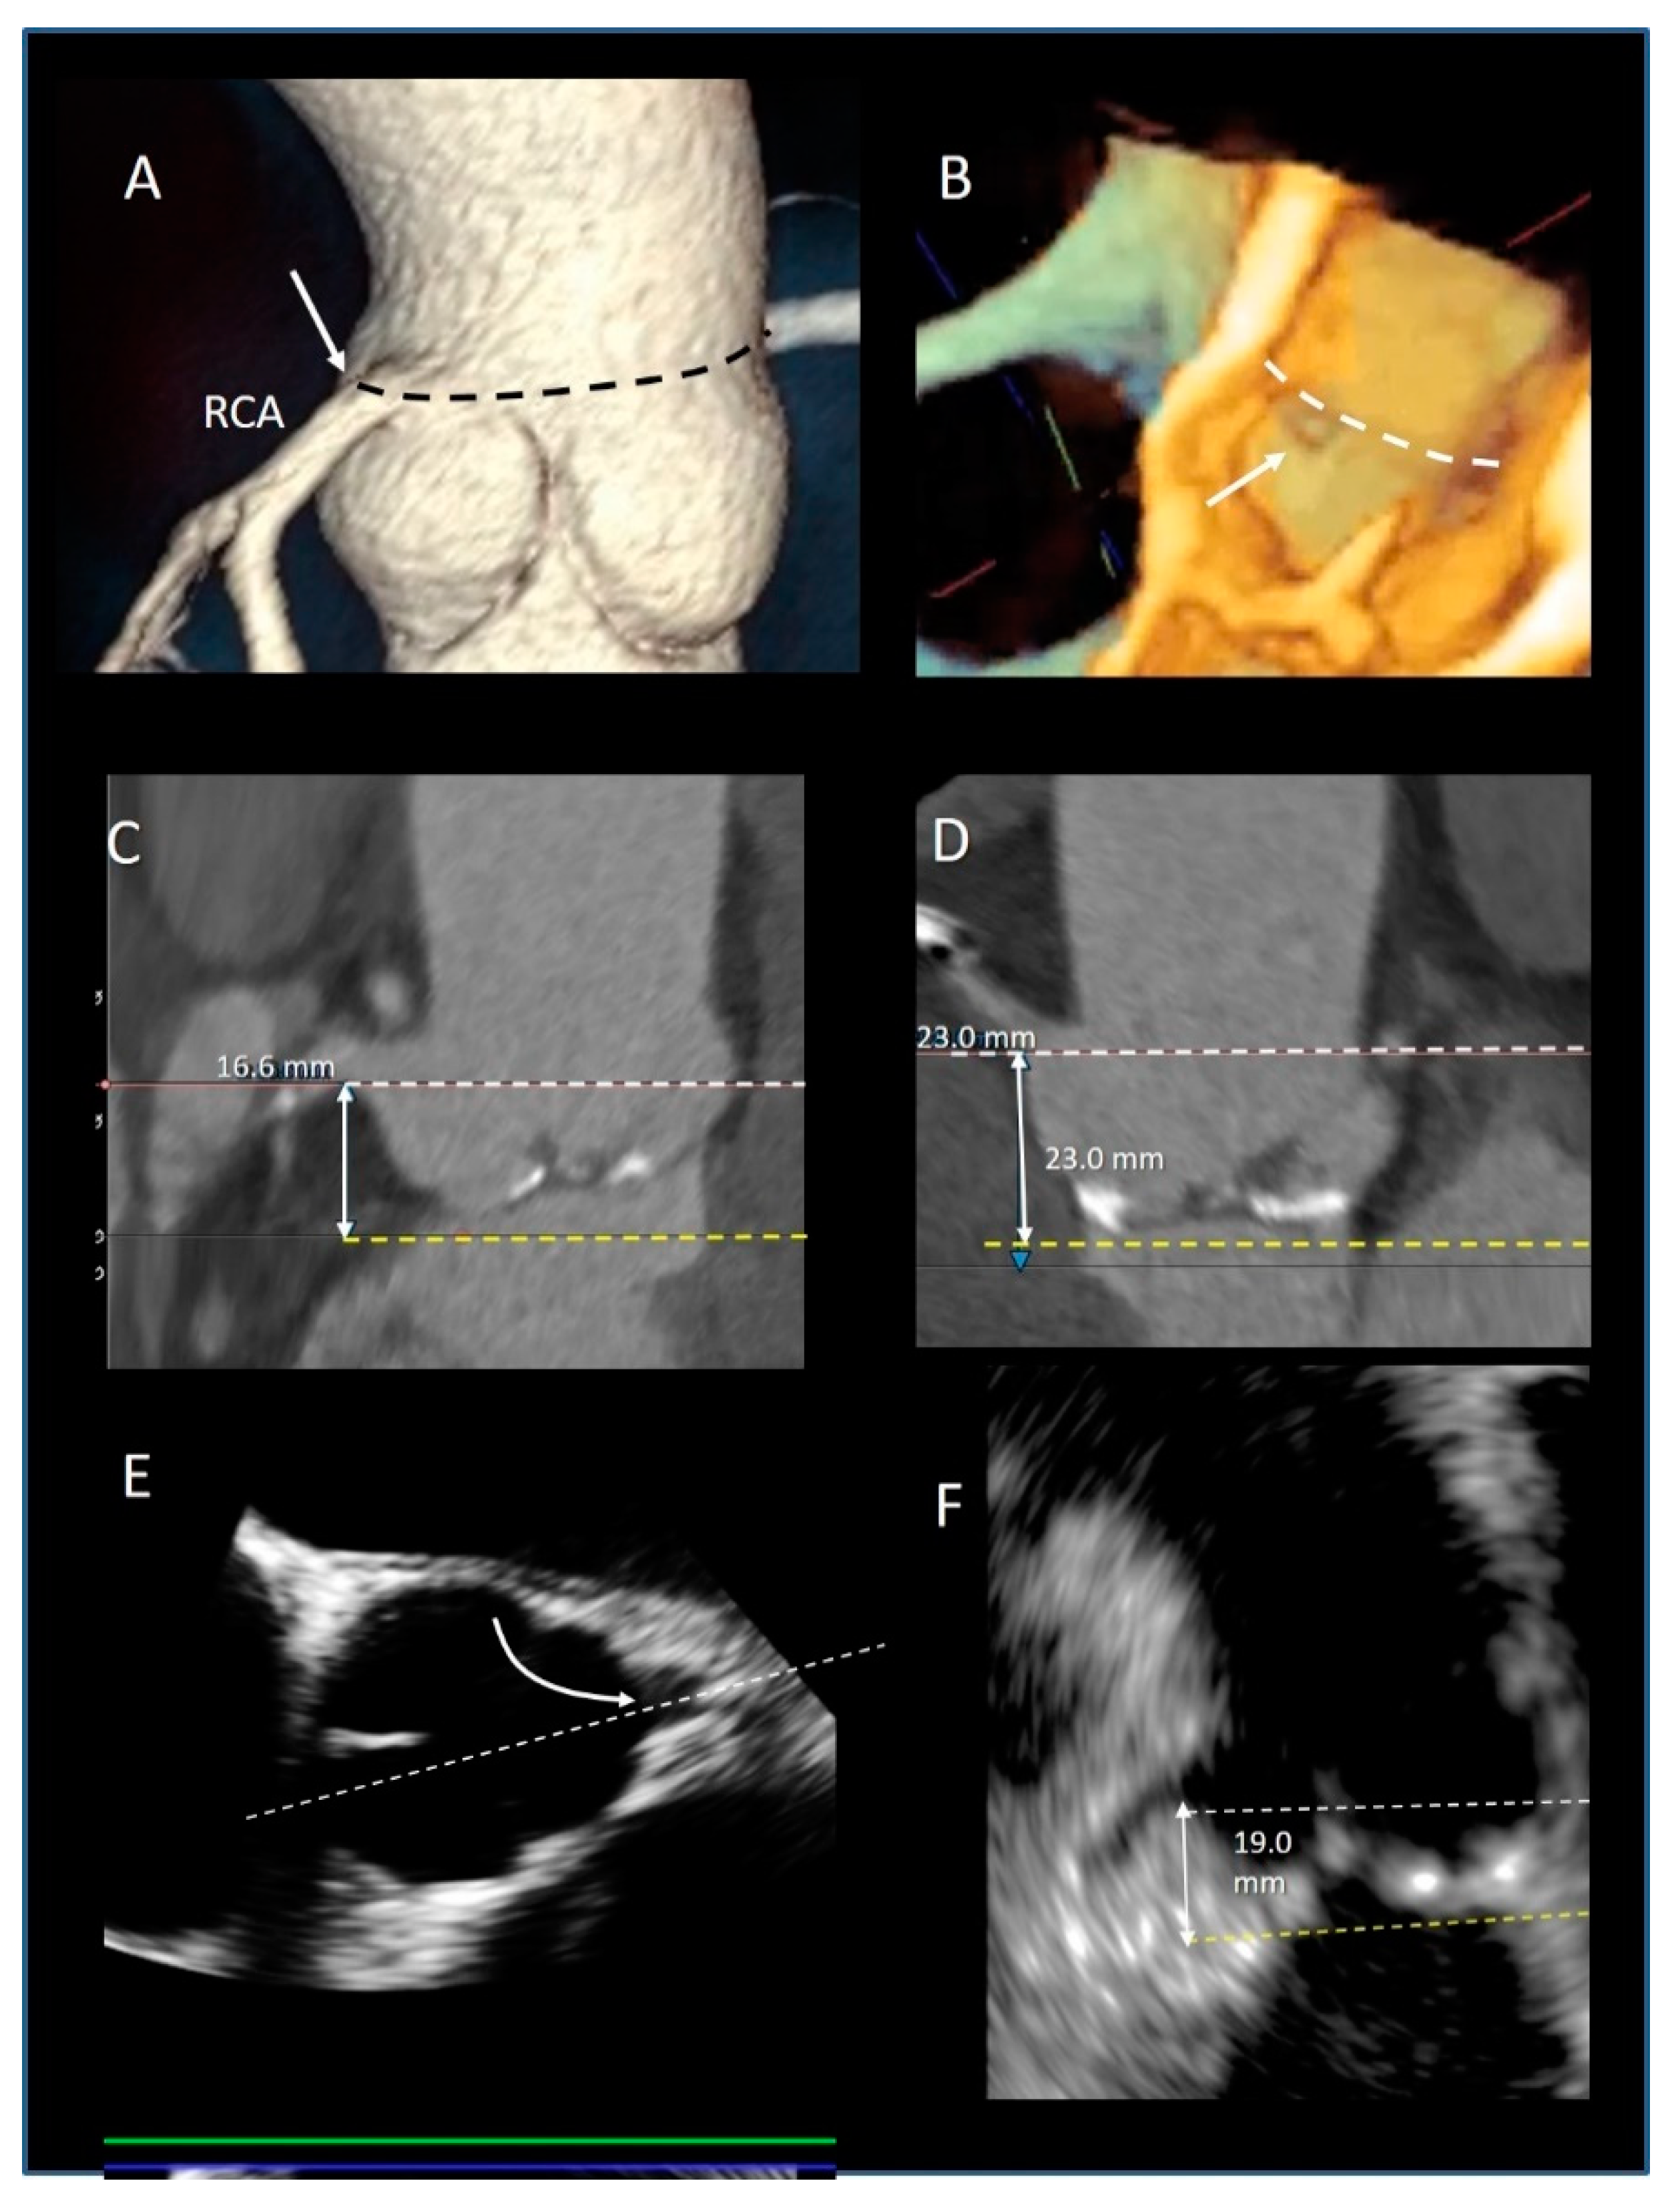

2. Aortic Root

3.10. The Coronary Ostia